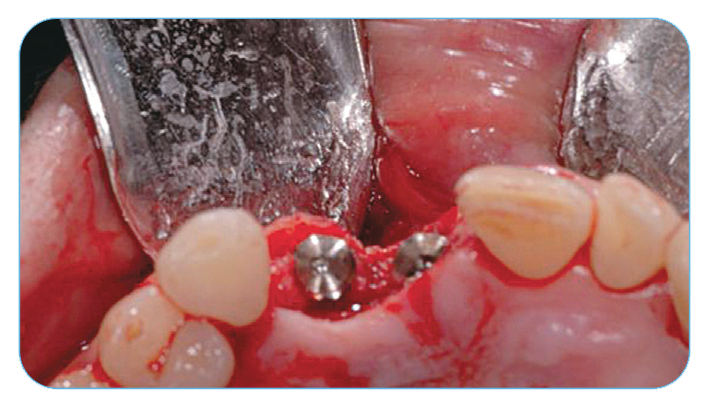

Anterior Ridge Augmentation

Fig. 2. Grafting with Endobon Xenograft Small Granules covered by an OsseoGuard® Resorbable Collagen Membrane.